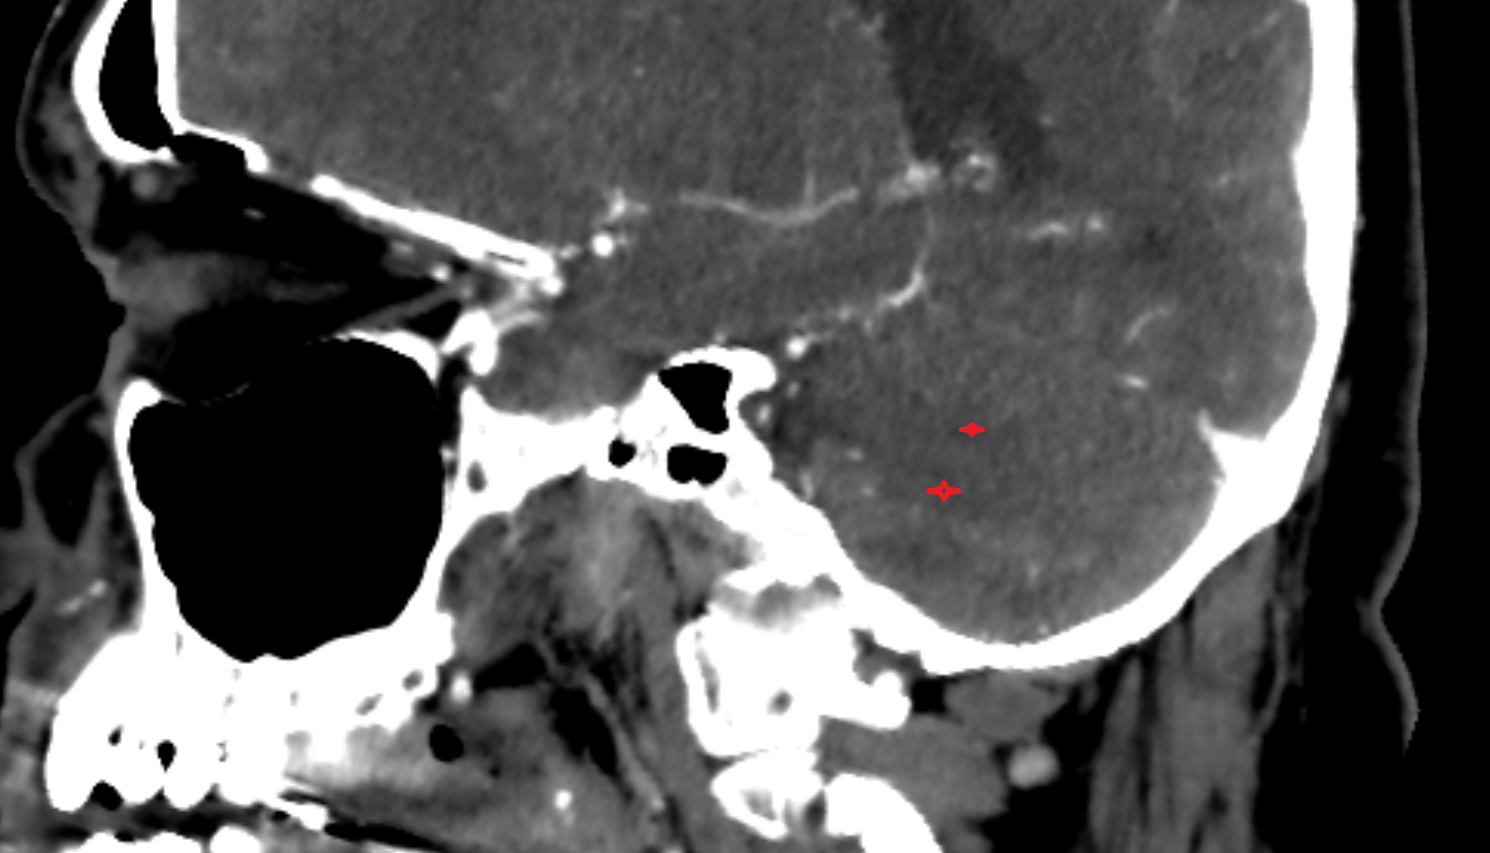

- Cerebellar tonsil (H IX)

- Tonsil of cerebellum

- Posterior cerebellomedullary cistern (cisterna magna)

- Cisterna magna